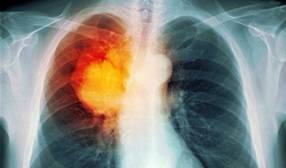

肺癌

作为世界范围内第一大常见肿瘤,肺癌也是临床科学研究的一大热门领域。据不完全统计,肺癌相关的国自然项目接近肿瘤项目总数的10%,每年发表SCI文章逾万篇。